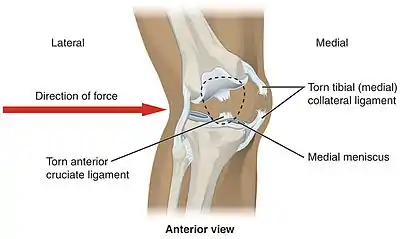

Lateral trauma to the knee can tear the medial collateral ligament, anterior cruciate ligament, and medial meniscus

Knee pain is caused by trauma, misalignment, degeneration, and conditions producing arthritis.[26] The most common knee disorder is generally known as patellofemoral syndrome.[26] The majority of minor cases of knee pain can be treated at home with rest and ice, but more serious injuries do require surgical care.[26]

In sports that place great pressure on the knees, especially with twisting forces, it is common to tear one or more ligaments or cartilages. Some of the most common knee injuries are those to the medial side: medial knee injuries.[29]